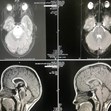

През месец юни тази година лекарите поставили на 11-годишно момиченце от американския щат Тексас страшна диагноза – злокачествен тумор на мозъка в последен стадий, който не подлежи на лечение.

За всеобщо учудване обаче, прогнозата им не се сбъднала. Освен това, към момента магнитният резонанс показва, че туморът е изчезнал безследно. Лекарите не могат да обяснят случилото се, тъй като, според научните данни, това е невъзможно, пише health.com, предаде БЛИЦ.

Медиците признават, че до момента не са се сблъсквали с подобна спонтанна и бърза регресия на голям злокачествен тумор на мозъка, т.е. случилото се може да се нарече само с една дума – истинско чудо.